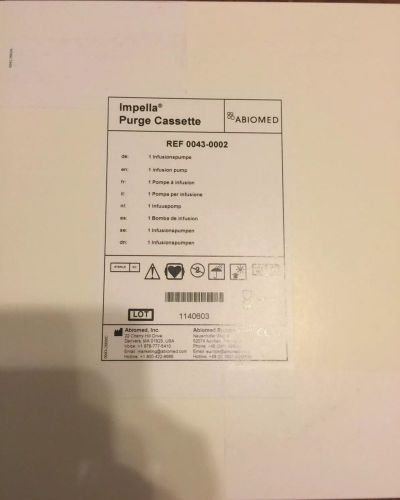

Abiomed Impella Purge Cassette Ref 0043-0002 New In Factory Box